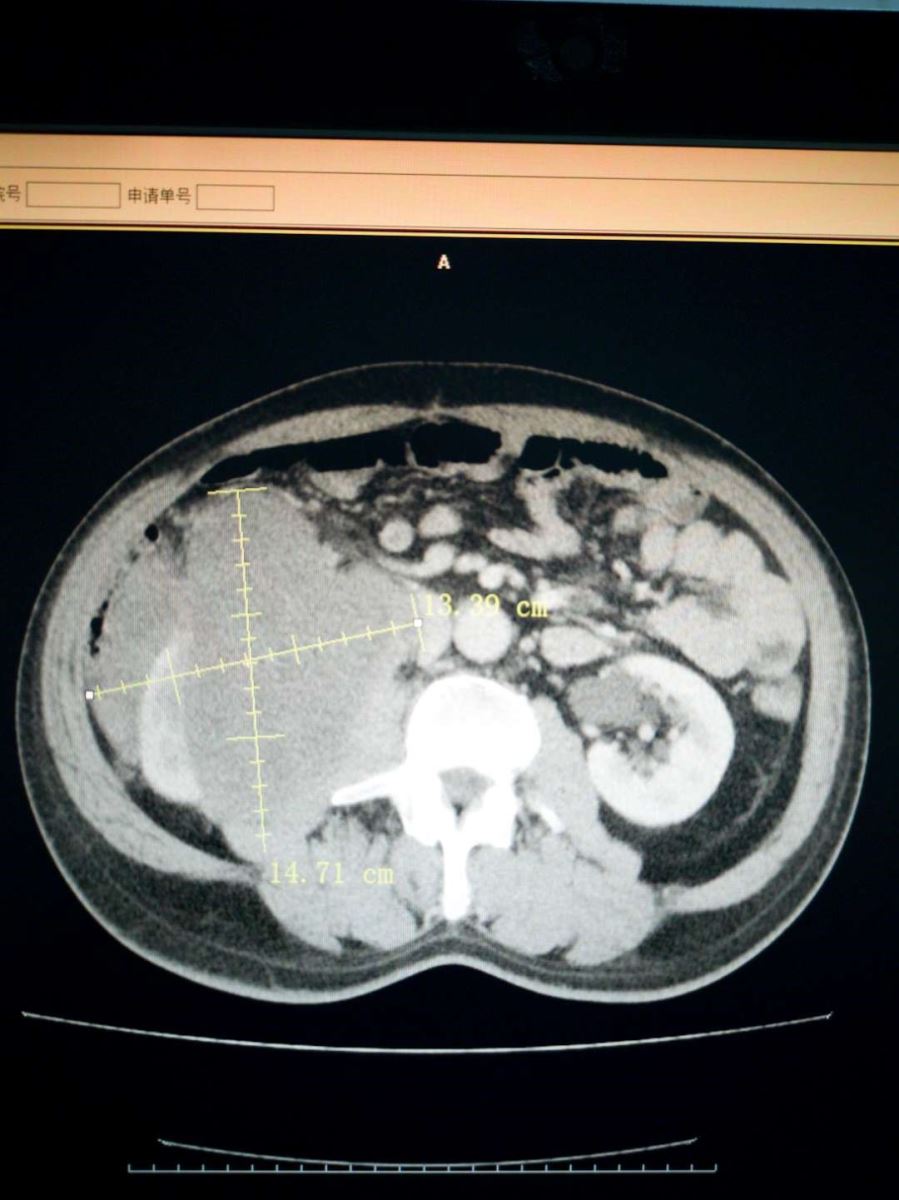

近日,西院肿瘤外科成功为一腹膜后脂肪肉瘤复发患者开展手术。患者于1年半前在外地某三甲医院被诊断为“腹膜后肿物”,行腹膜后肿物切除术,术后病理诊断为“腹膜后脂肪肉瘤”。此后定期复查,1月前,患者自觉左侧腹部可触及包块,伴疼痛,腹胀,食欲下降,消瘦明显。在外院查腹部彩超提示:腹膜后肿物。患者为进一步治疗,来我院。入院后完善检查,进一步明确诊断。全腹增强CT提示:右中腹见团块状混杂密度影,形态不整,右肾变形,内部密度不均,与下腔静脉、胰头、十二指肠,右侧腰大肌关系密切,增强扫描呈混杂密度影。肿瘤外科全体医生对患者病情进行了细致详尽的术前讨论。患者1年半前行腹膜后脂肪肉瘤切除术,此次考虑为腹膜后脂肪肉瘤复发,肿瘤较大,与周围器官关系密切,尤其紧邻下腔静脉,二次手术风险极大,一旦发生下腔静脉意外撕裂,可能造成空气栓塞等致命性危险。全科医生一起反复仔细查阅增强CT,制定详尽的手术计划。并对可能出现的风险及意外进行预判,提出解决方案。与患者家属沟通,详细交待病情,说明治疗方案及手术风险。